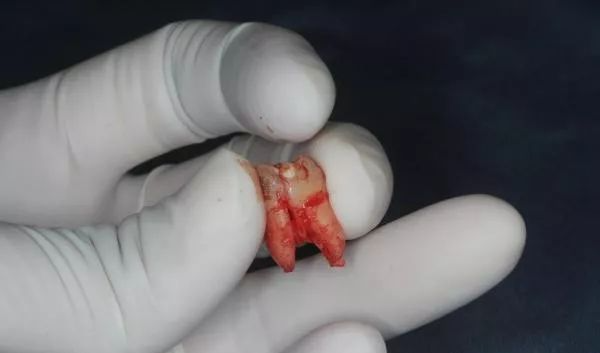

回到剛剛那個(gè)牙齒,它依次被撬出來(lái)之后是這樣的:

圖片來(lái)源:作者提供

我甚至還可以把它們拼起來(lái)~

是吧,這樣的智齒「拔」大概是要花點(diǎn)功夫了。